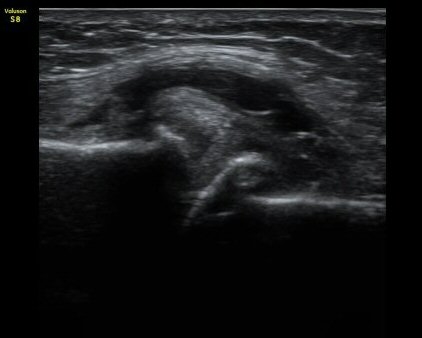

ÃÊÀ½ÆÄ °Ë»ç

¹«¸­ ³»Ãø Á¾´Ü¸é°Ë»ç¿¡¼­ °üÀý°£°ÝÀÇ °¨¼Ò ¹× ¹Ý¿ùÆÇ¿¬°ñÀÇ ÅðÇ༺ º¯È­¿Í ¿ÜÃø À¸·Î µ¹Ãâ¿¡

ÀÇÇÑ ³»Ãø ÃøºÎÀδëÀÇ ½ÉÇÑ ¿ÜÃø µ¹Ãâ º¯ÇüÀ» º¸ÀÌ°í ³»Ãø ÃøºÎÀδë¿Í ¹Ý¿ùÆÇ¿¬°ñ »çÀÌ¿¡ ¹«¿¡ÄÚ

¼ö¾× Àú·ù°¡ °üÂûµÊ. °æ°ñ°ú ´ëÅð°ñÀÇ °ñ±ØÀÌ ¸Å¿ì ½ÉÇÑ »óÅÂÀÓ(±×¸² 1, 2).

°üÀý³»Ãø Á¾´Ü¸é°Ë»ç(ÁÖ»ç »çÁø 1)  À§Ä¡¿¡¼­ ³¶Á¾ ÈíÀÎ ÈÄ ÁÖ»çÄ¡·á ½ÃÇàÇÔ(ÁÖ»ç µ¿¿µ»ó 2).